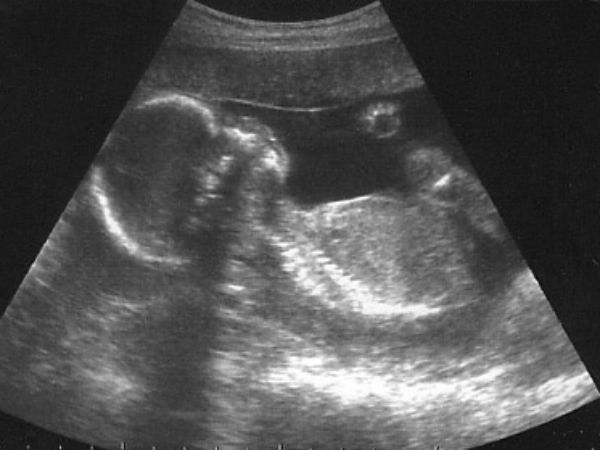

ஜெய்பூர்: கருவில் இருக்கும் குழந்தை ஆணா, பெண்ணா என்பதை கண்டறியும் பாலின பரிசோதனை மீதான தடை நீக்கப்படக்கூடும் என்று மத்திய அமைச்சர் மேனகா காந்தி தெரிவித்துள்ளார்.

கருவில் இருக்கும் குழந்தை ஆணா, பெண்ணா என்பதை கண்டறியும் பாலின பரிசோதனை மீதான தடையை நீக்குவது குறித்து மத்திய அமைச்சரவை ஆலோசித்து வருகிறது. மேலும் கருவில் இருக்கும் குழந்தை ஆணா, பெண்ணா என்பதை கண்டறிவது கட்டாயம் ஆக்கப்படும்.

அப்படி குழந்தை ஆணா, பெண்ணா என்பது கண்டறிந்து பதிவு செய்யப்படும். கருவை கலைத்தால் அதற்கான காரணத்தை தெரிவிக்க வேண்டும் அல்லது மருத்துவ சான்றிதழ் அளிக்க வேண்டும். இந்த புதிய முறை மூலம் கருவிலேயே பெண் குழந்தைகள் அழிக்கப்படுவதை தடுக்க முடியும்.

பாலினத்தை கண்டறிந்தவுடன் அது குறித்து பதிவு செய்யப்படுவதால் வீட்டில் பிரசவம் பார்க்கும் முறைக்கு முற்றுப்புள்ளி வைக்க முடியும். வீட்டில் பிரசவம் பார்க்கையில் பெண் குழந்தையை கொலை செய்ய வாய்ப்பு உள்ளது.

தடையை மீறி அதிகாரம் படைத்த சிலர் கருவில் இருக்கும் குழந்தையின் பாலினத்தை கண்டறிந்து அதை கலைத்து வருகிறார்கள். ஏற்கனவே நிரம்பி வழியும் சிறைகளில் மேலும் பலரை அடைக்க விரும்பவில்லை என்றார்.